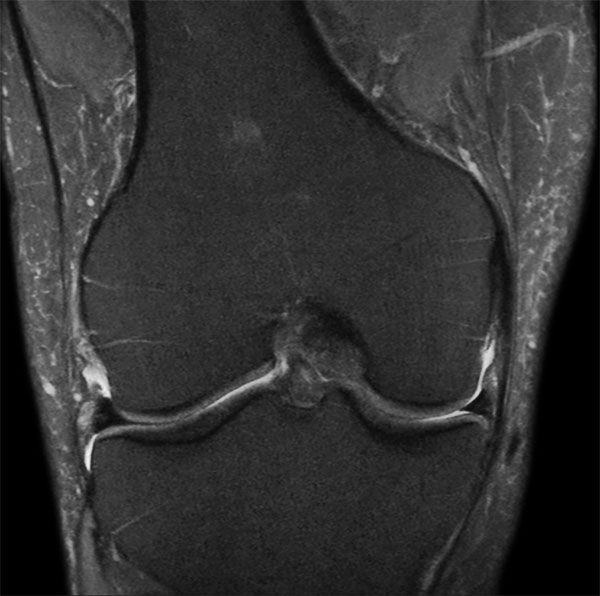

Middle aged board surfer presents with chronic knee pain. X-Ray shows no abnormalities. Follow-up MR examination requested.